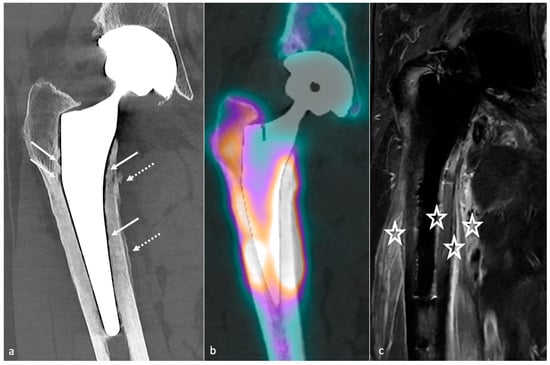

4.3.3. Radiographs, Tomosynthesis, and CT

4.3.4. MRI

4.5.2. Classification and Contribution of Imaging Methods

- Metallosis results from the shedding of metallic debris (secondary to a MoM prosthesis with corrosion, a conflict between a metallic acetabular cup and the prosthetic neck, or a contact between a metallic head and an acetabular metal back in case of PE wear or dislocation) that induces synovitis and an indolent pattern of osteolysis, potentially leading to loosening (i.e., potentially looking similar to osteolysis and PE wear). Synovitis may contain low-signal intensity or metallic density debris, causing MRI artifacts and bone erosion, best depicted on CT-MAR (Figure 20). Such debris might also be located in periprosthetic soft tissue and lymph nodes [54,57]. Metallic debris presence might also accentuate PE wear (i.e., third fragment wear) [54]. Of note, high serum metal-ion levels can be found in symptomatic and asymptomatic patients and would be associated with pseudo-tumors, so that such a biological finding should lead to the prescription of an MRI to rule out a pseudo-tumor even in asymptomatic patients [6,103].

- Additionally, referred to as trunnionosis, trunnion corrosion corresponds to a soft-tissue reaction to metal debris released from micromotion and mechanical wear at the head–neck or neck–stem junction of modular MoP HA. On MRI, it manifests as an adverse local reaction associated with medial calcar resorption [11,104].